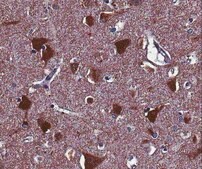

免疫组化分析:代表性批次的1:500稀释液在人和小鼠大脑皮层组织切片中检测到Homer1。